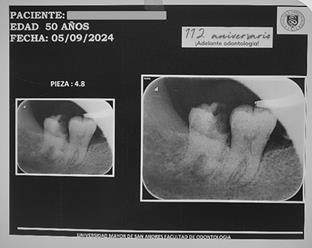

Para planificar la conducta terapéutica de la pieza 4,8 se solicitó una radiografía periapical, que evidenció la dilaceración de las raíces y la calcificación de los conductos radiculares; a nivel periapical se observó un área radiolúcida (Figura 3). Por lo que se sugirió como una opción terapéutica la exodoncia de la pieza 4.8.

Figura 3. Radiografía periapical de la pieza 4,8. Tercer molar con raíces dilaceradas y calcificación de conductos radiculares.